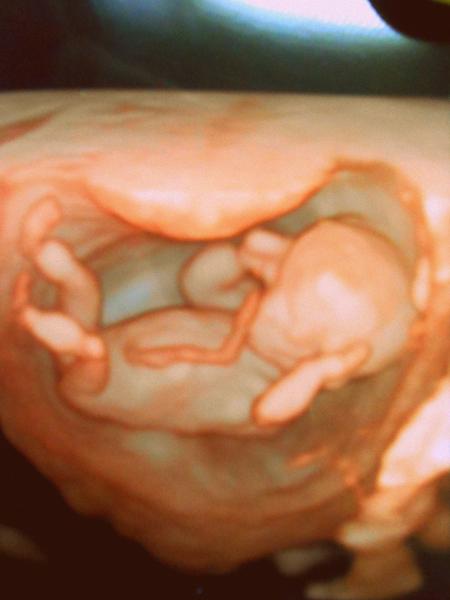

3D ultrazvuk v 10. týdnu těhotenství. Má smysl?

Já kdyby byla možnost, tak bych tedy 3D fotečku brala 🙂, i takhle na začátku, koukni takhle by jsi mohla mít prcka zachyceného, mně to přijde úžasné 😵

jasne,z e jo. v 10tt se ti alespon prcek vejde v cely/a na foto 😉 to uz se ve 20tt nevejde 😉

V 10tt je to spis mimozemšťan - dle mého zbytečnost, mimco hezke nebude .... já mám 3d fotku z 12tt, 20tt a 22tt - všechny fotky jsem měla zdarma na cilenem 3d ultrazvuku jsem nebyla ... Jinak 3d ultrazvuk nemá z medicínského hlediska vůbec zádný vyznam - to co píse kammka, tak to vse lékař určuje klasickým ultrazvukem

@simdan tak tohle je nádherna fotka. Já byla asi v 25 tt a takhle to Teda nevypadalo. Bylo to zase jiný no 🙂